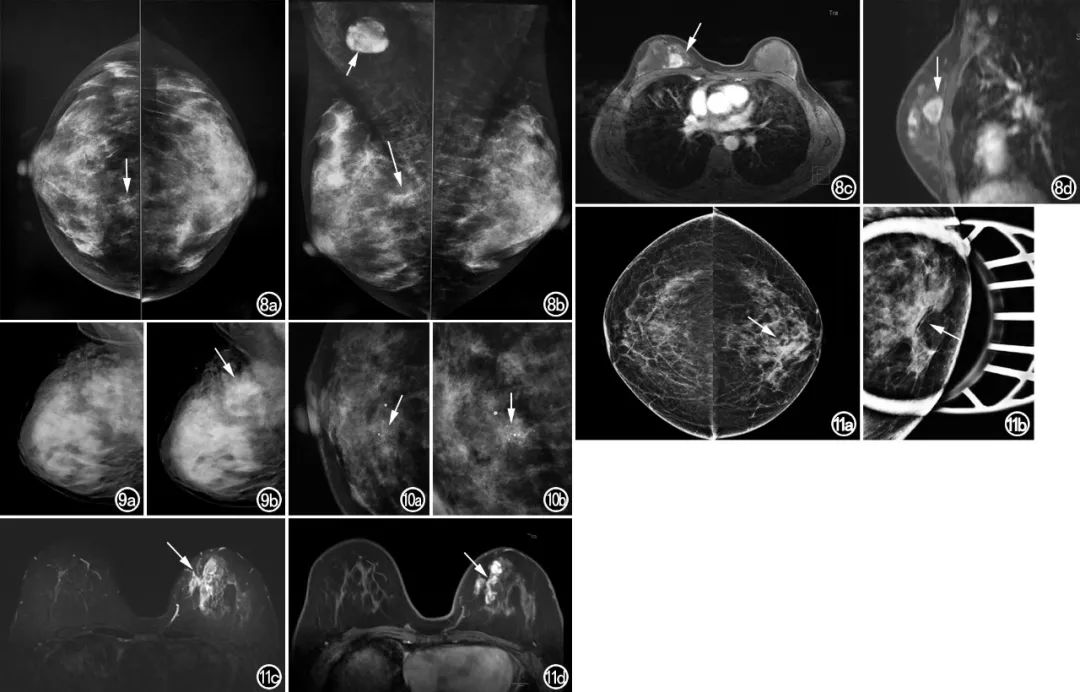

文献报道乳腺癌表现为不对称的主要原因包括:①癌细胞沿乳腺导管浸润扩展而不形成明显的肿块;②癌周无增生的纤维组织包绕,使肿块缺乏明确的边界;③癌周炎性反应较显著,遮盖大部分或全部肿块;④肿块密度较低,接近正常腺体密度,且周围存在较丰富的腺体,使肿块淹没其中,两者缺乏明确的界限。部分乳腺X线摄影表现为局灶不对称的病变,超声或MRI检查证实为肿块(图8)。因此,乳腺X线摄影上新发或进展性不对称与临床/超声发现的肿块位置相对应时,应警惕恶性肿块的可能。

微小钙化是DCIS常见的X线表现。90%乳腺癌微小钙化灶为原位病变,其中80%为DCIS。钙化多为细小多形性、线样分枝状,部分为模糊不定形或粗糙不均质钙化。分布方式以线样、段样及簇状为主。当原位癌局部早侵合并钙化分布区腺体密度增高时,表现为局灶性不对称,范围较广则表现为整体不对称。DCIS表现为不对称伴微钙化较容易诊断,但部分仅表现为不对称(图11),合并或不合并周围腺体结构改变,此时容易误诊。MRI能发现乳腺X线摄影、超声等无法检出的乳腺癌。段样、线样非肿块样强化被认为是DCIS MRI增强后的特征性表现形式,对DCIS的诊断具有很高的特异性。集簇状、成簇环形强化是诊断DCIS的重要征象,结合其特征性的强化方式,诊断正确率明显提高。MRI评估DCIS的范围较X线摄影检查等更为准确。

图8 女,45岁,浸润性导管癌。a)双侧乳腺X线摄影CC位示右乳内上象限局限性密度增高影,密度欠均匀,其内似见浅钙化(箭);b)MLO位示右乳内上象限局限性密度增高影,形态及范围与CC位所见类似,密度欠均匀,周围腺体结构稍紊乱,血管影稍多(长箭),右腋区淋巴结肿大(短箭),密度增高,淋巴结门消失;c)横轴面T1WI增强示右乳内上象限卵圆形肿块,边缘欠清,增强后明显不均匀强化(箭),与乳腺X线摄影所示局灶性不对称伴钙化区域位置一致;d)矢状面T1WI增强示右乳内上象限肿块,病灶粘连邻近浅筋膜深层(箭)。

图9 女,49岁,乳腺浸润性导管癌。a)右乳X线摄影MLO位示乳腺为极度致密型乳腺,乳内未见明显异常征象;b)4个月后,MLO位示右乳上份局灶性不对称,病灶密度欠均,其内伴模糊不定形钙化,周围腺体结构紊乱,血管影增多(箭)。

图10 女,52岁,乳腺浸润性导管癌。a)右乳X线摄影CC位局部放大影像示右乳中央区局限性密度增高影,密度欠均匀,其内伴粗糙不均质钙化(箭);b)MLO位局部放大影像示右乳中央区局限性密度增高影,与CC位所见病灶形态、大小一致,病灶密度欠均匀,内见粗糙不均质钙化,周围腺体结构紊乱,血管影增多(箭)。

图11 女,43岁,乳腺DCIS。a)双侧乳腺X线摄影CC位示左乳内侧局灶性不对称,密度欠均匀,小梁结构稍粗(箭);b)左乳X线摄影点压切线位示左乳内上象限局灶性不对称,密度欠均匀,未见恶性钙化,周围腺体结构紊乱,血管影增多(箭);c)横轴面T2WI平扫示病灶呈稍高信号,周围腺体水肿样改变(箭);d)横轴面T1WI增强示病灶呈段样不均匀强化,内部呈集簇状强化(箭)。